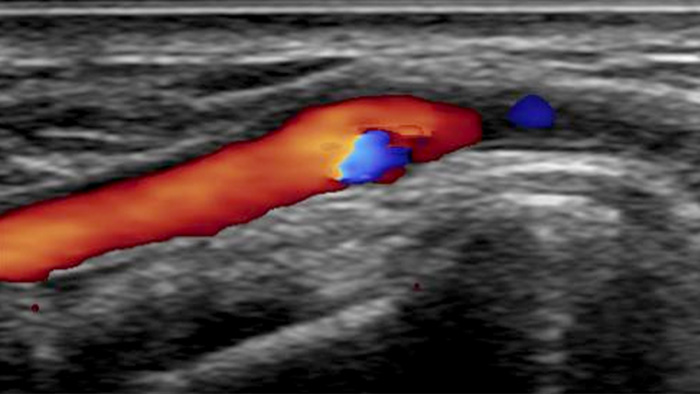

A realistic visualization of arterial vasculature is required to effectively access the arterial system. Our integrated CX50 ultrasound system provides premium quality images of the radial artery and veins to support radial access interventions.